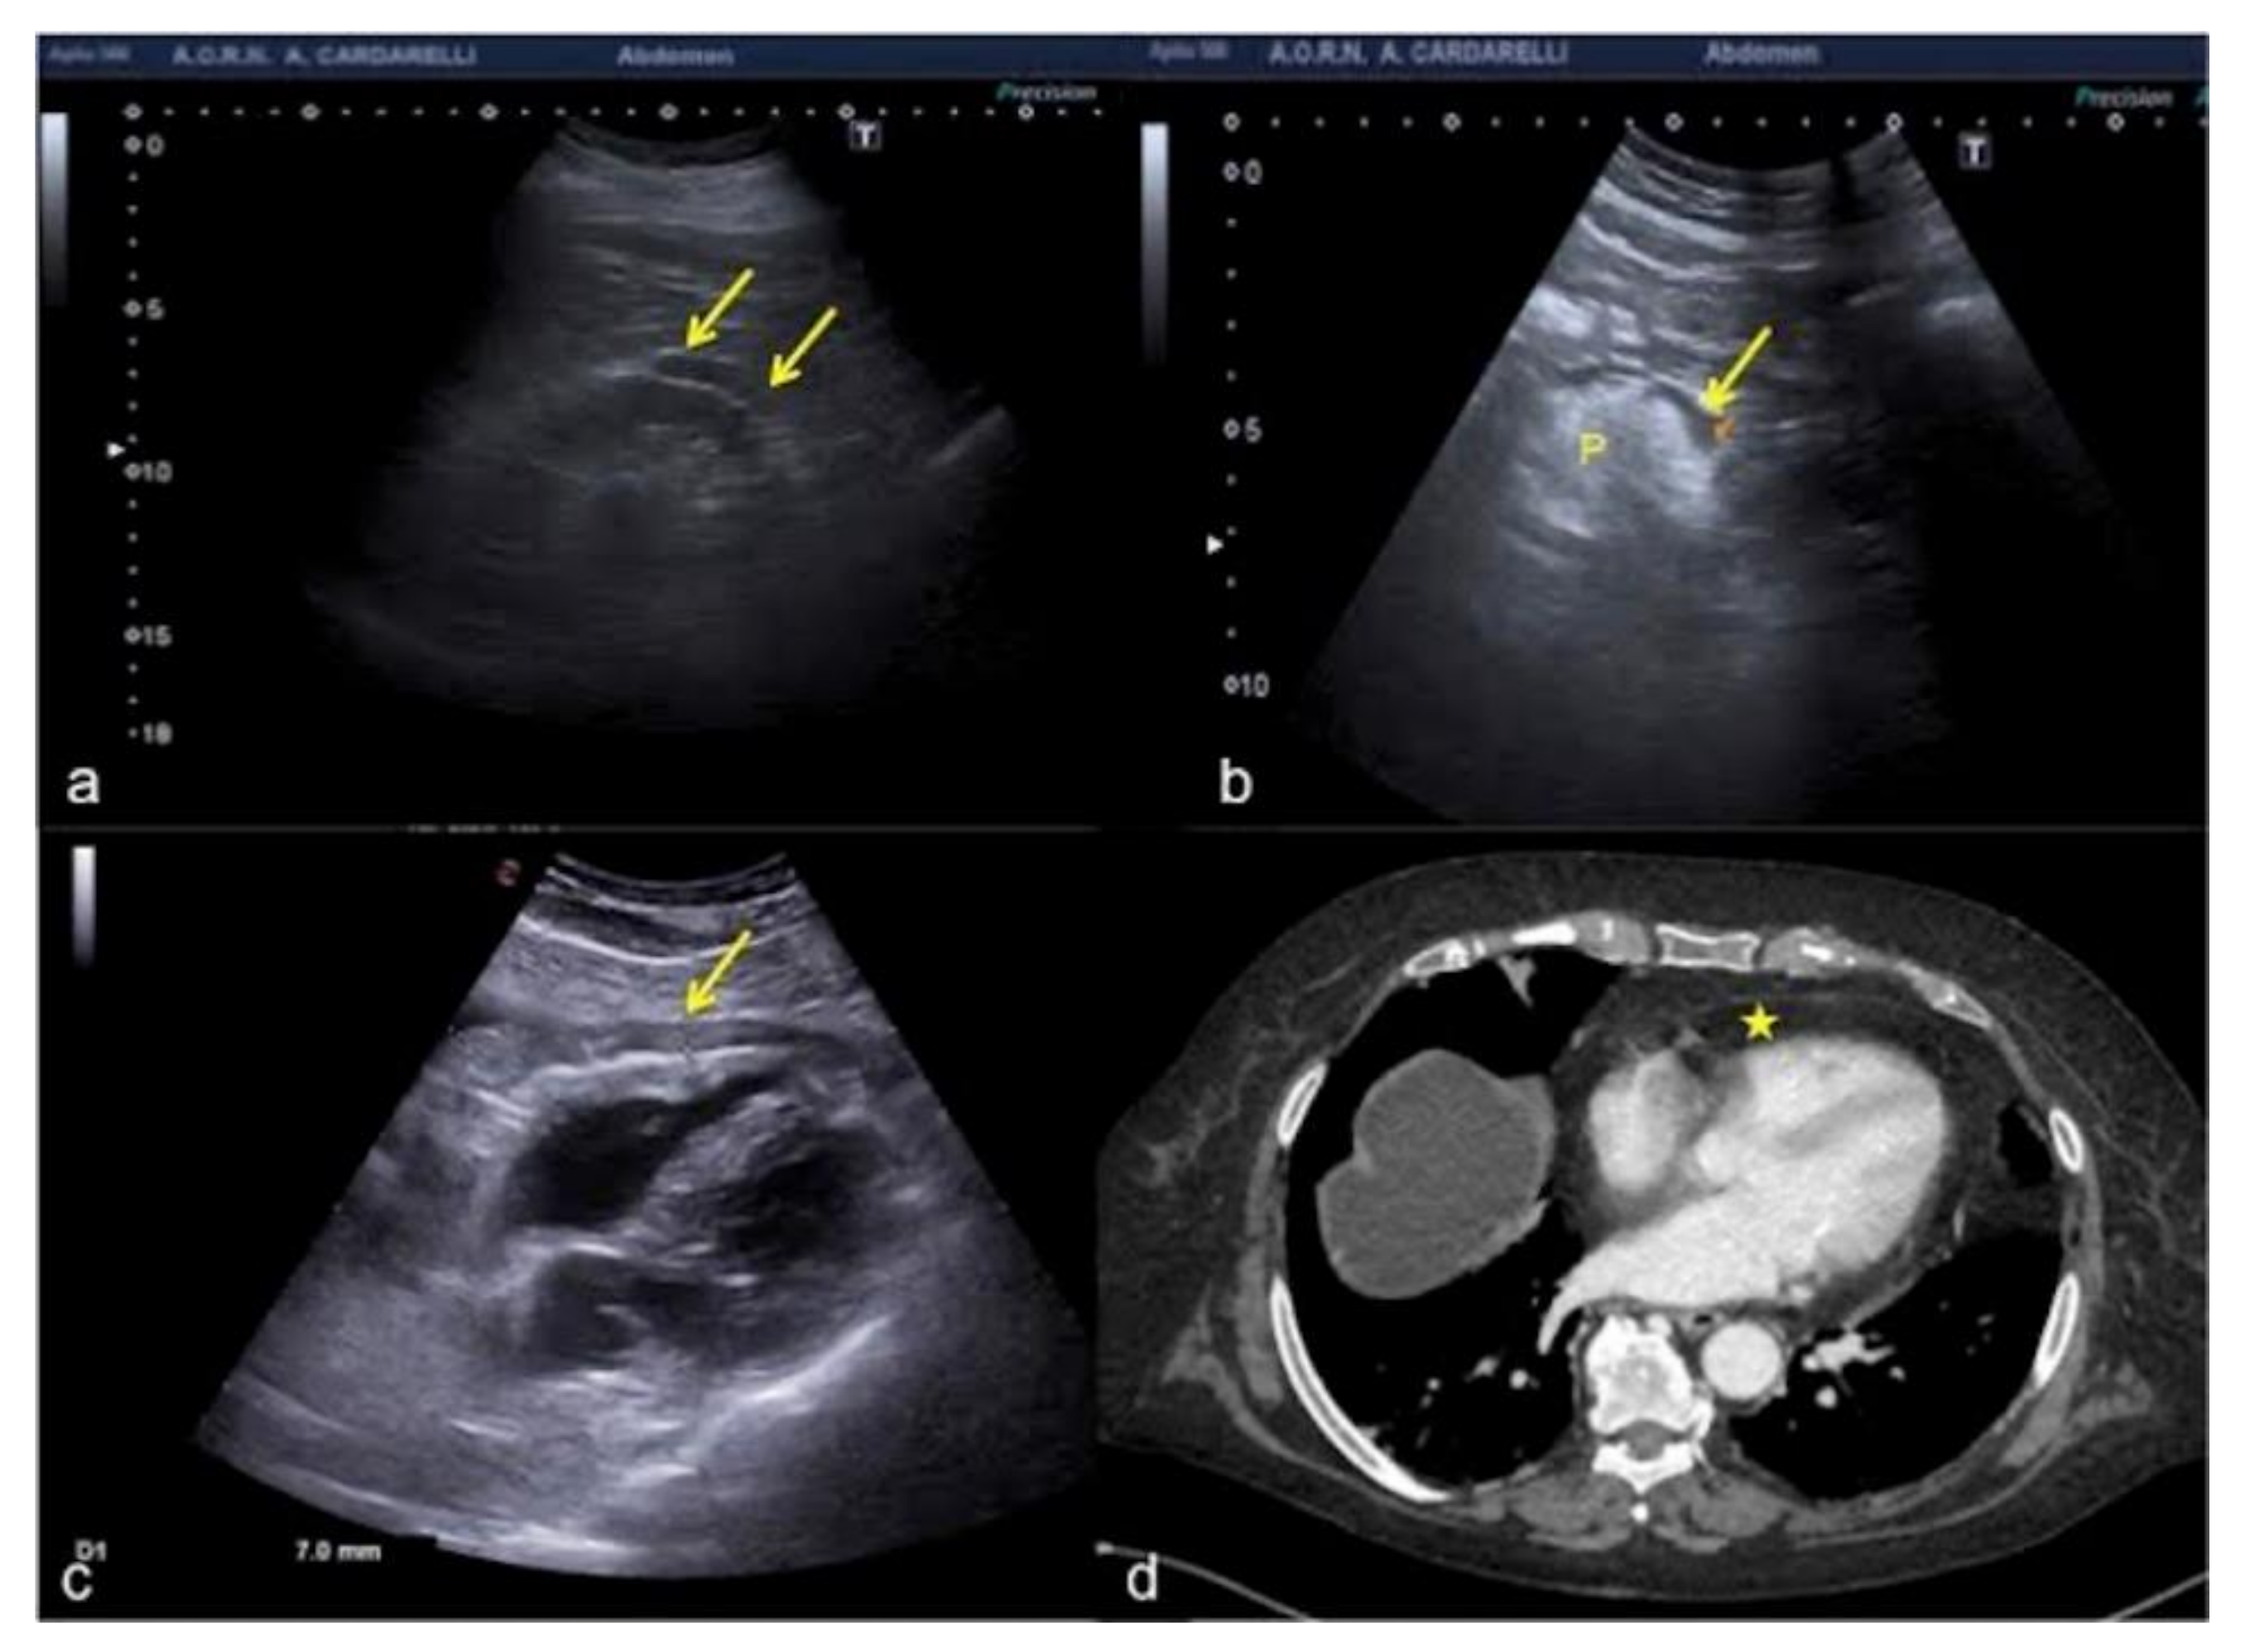

3.1. Bad Artifacts

3.1.1. The Side Lobe Artifact